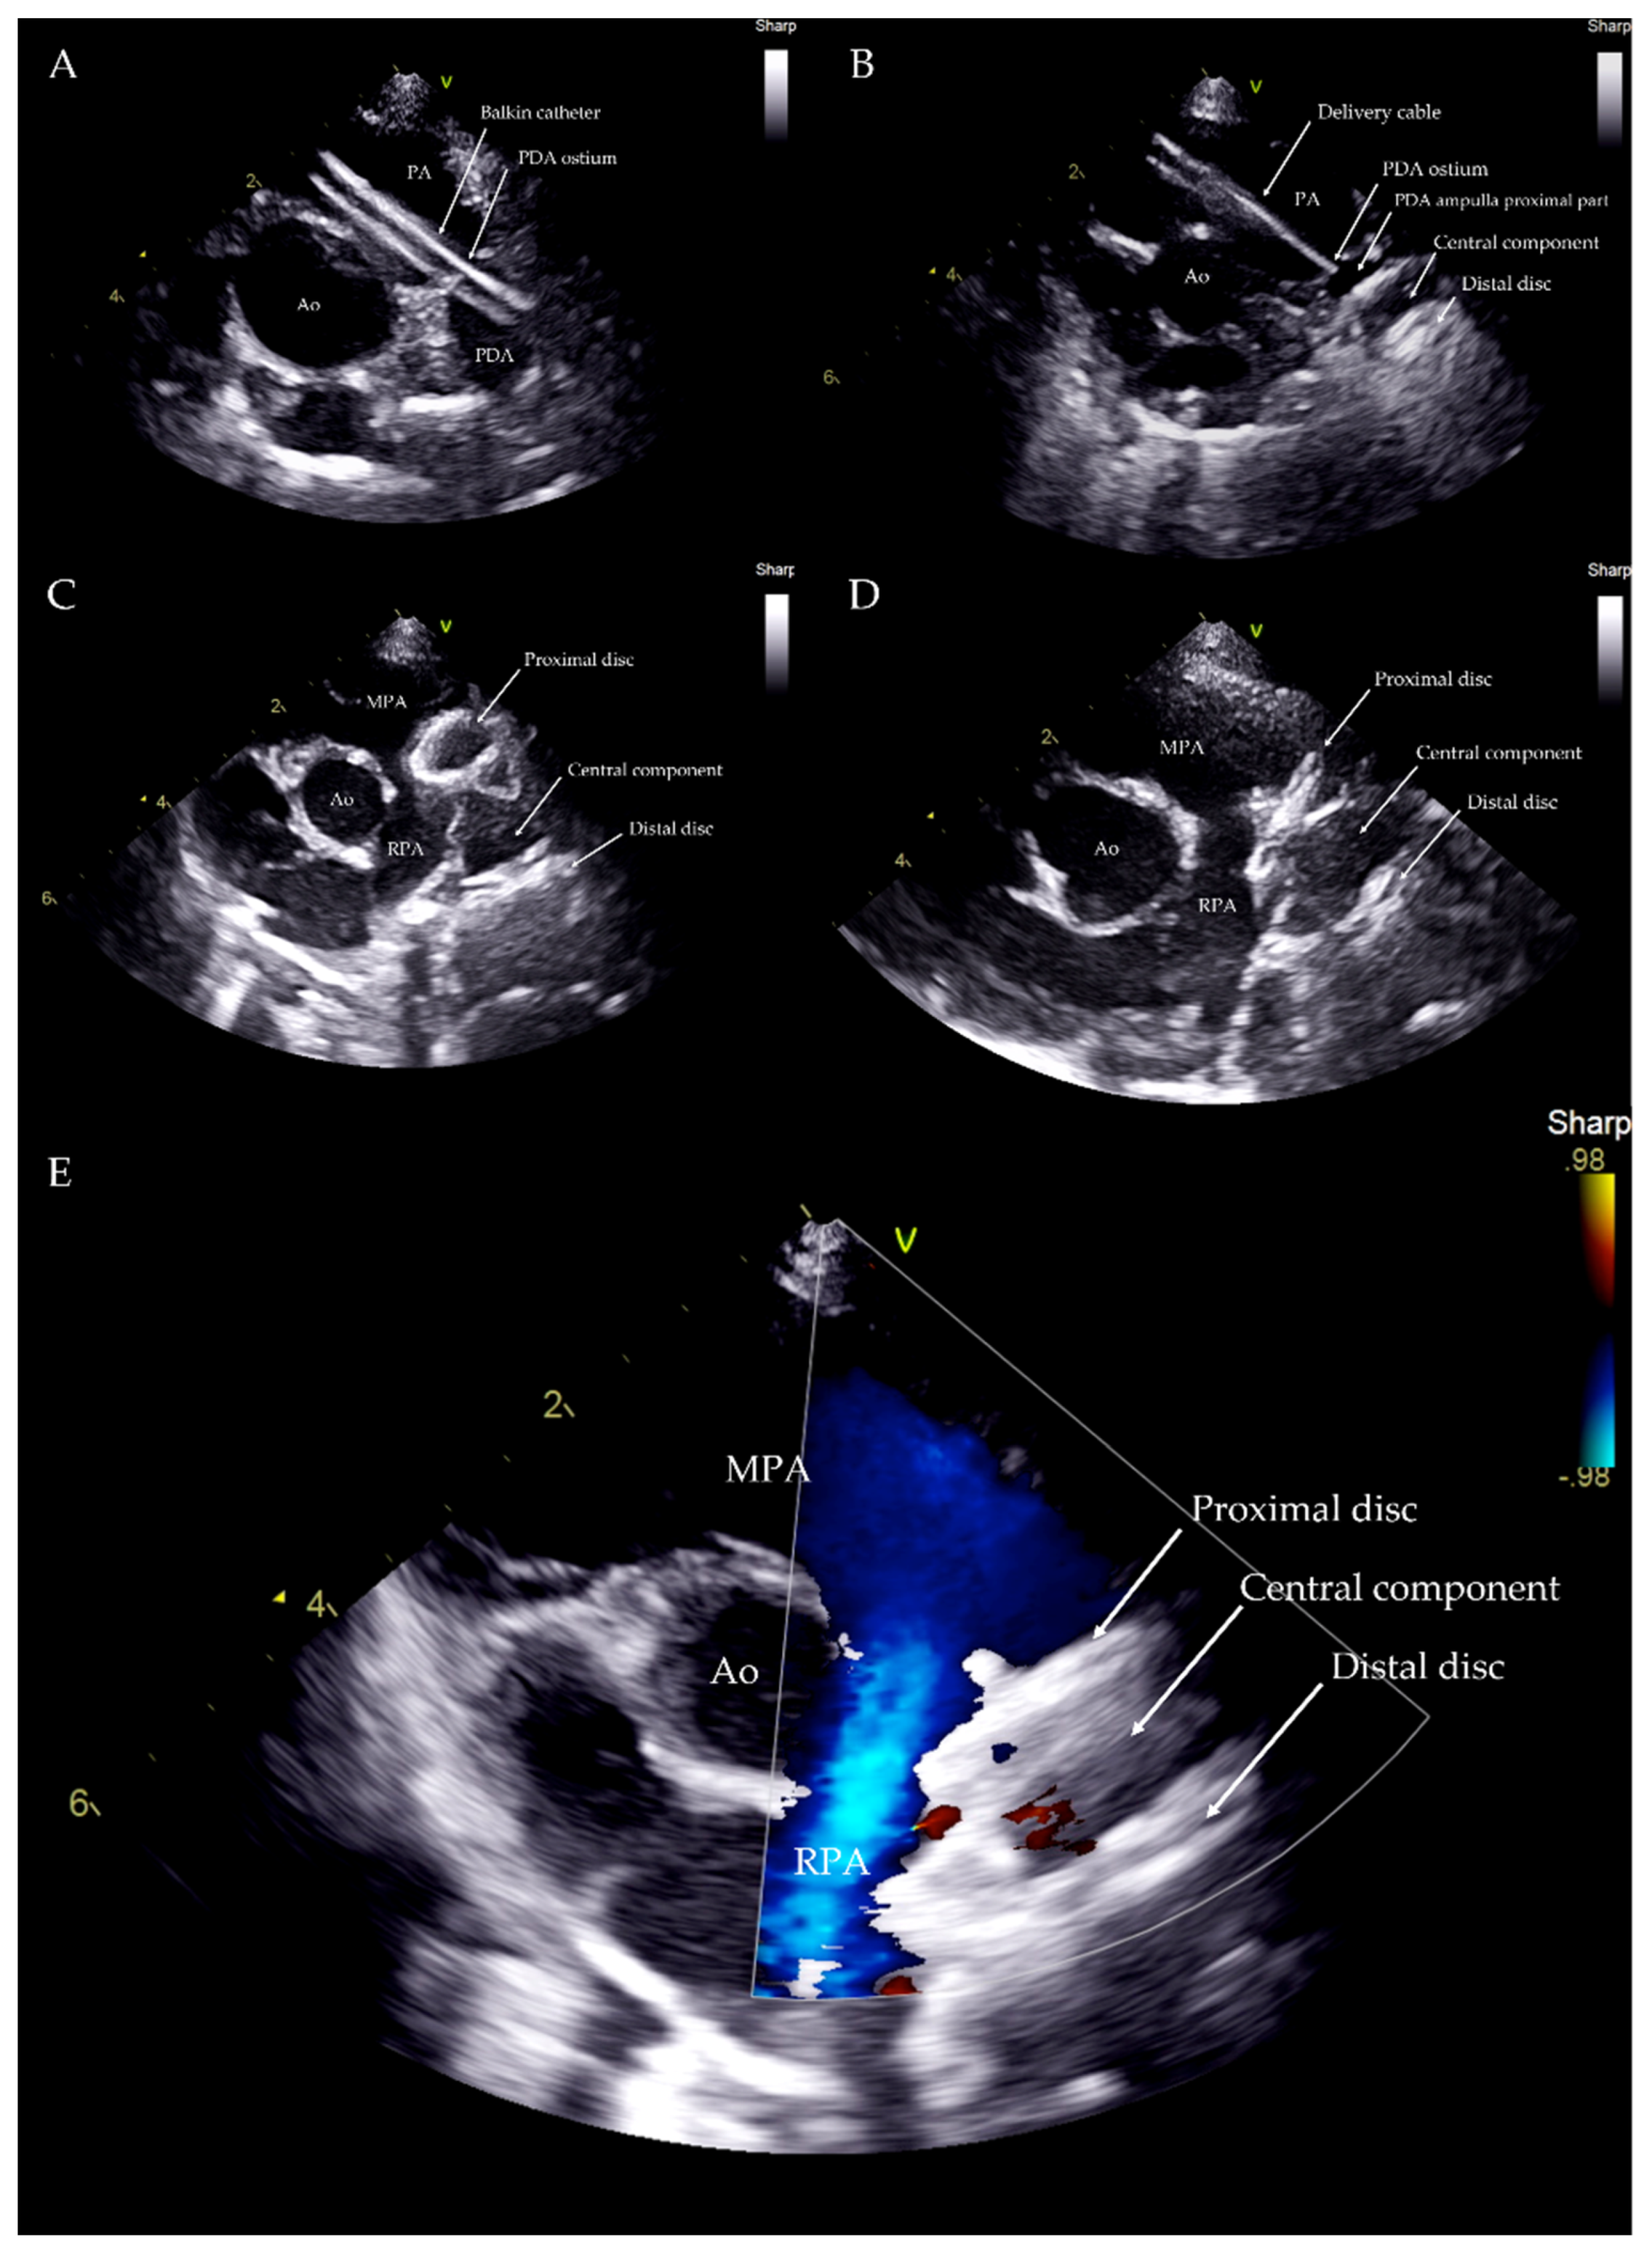

Correct positioning of the device was also evaluated during the procedure using transthoracic echocardiography, which also enables the presence or absence of residual flow to be analyzed throughout the device as well as its stability within the duct (Figure 5).

Figure 5. Transthoracic echocardiography from left parasternal cranial view during the procedure. Balkin catheter through the PDA (A). Distal disc and central component within the PDA ampulla (B). Distal disc and central component within the PDA ampulla and proximal disc within the PA just before the device deployment (C). Device released within the PDA structure (D). Device within the PDA with no residual flow (E). Ao: aorta; PA: pulmonary artery; MPA: main pulmonary artery; RPA: right pulmonary artery; V: probe marker.